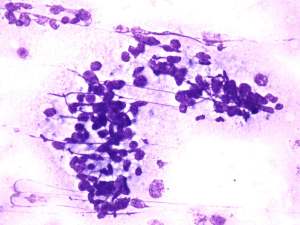

Cytology: suspicion of non Hodgkin lymphoma.

The cytological picture was identical with a small cell malignant tumor. Differential diagnostics included a metastatic small cell lung tumor and malignant lymphoma. The clinical presentation substantially decreased the likelihood of the former.